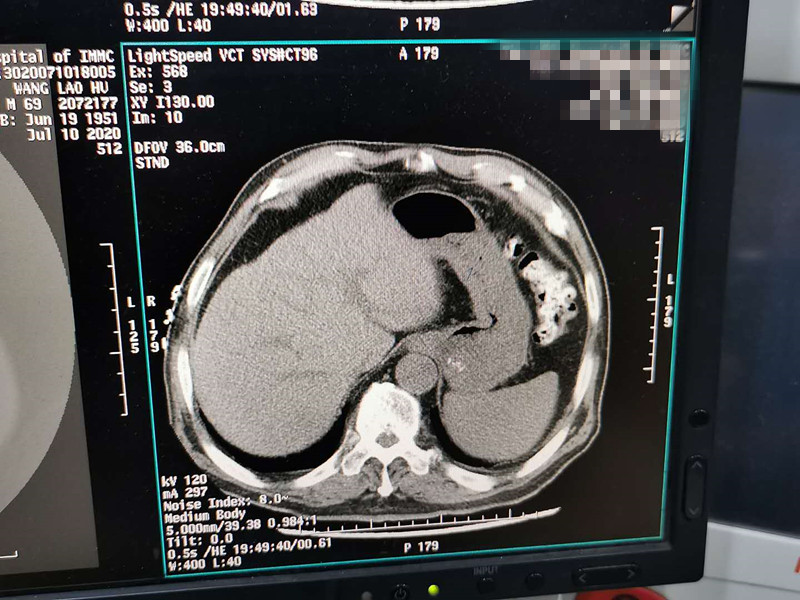

83岁肺部氩氦刀冷冻消融

发布人:美国氩氦刀技术官方网站    发布时间:2020/7/20 15:28:22